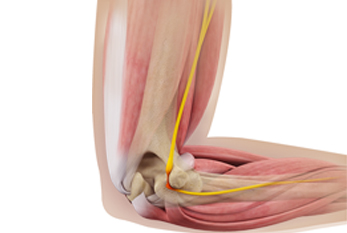

Cubital Tunnel Syndrome

This is due to compression of the ulnar nerve behind the elbow. It gives rise to pain, numbness, and tingling in the ring and little finger. It can also cause weakness of the muscles in the hand. Nerve tests are often required to confirm the diagnosis. Depending on symptoms, the nerve can be released and the compression removed. Diagnosis can often be made by a careful history and examination and this can be provided by the team at shoulder, elbow, hand.